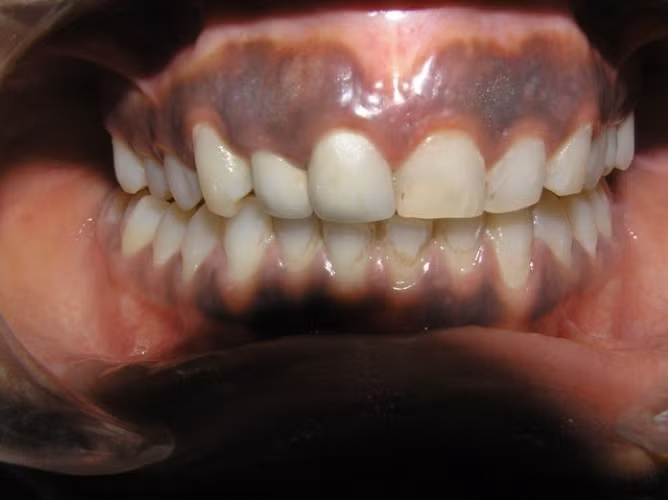

Đường viền Burton quanh chân răng của bệnh nhân nhiễm độc chì. Ảnh minh họa.

Ở mức độ rất cao, nhiễm độc chì có thể gây tử vong. Một triệu chứng đặc hiệu khi trẻ nhiễm độc chì mạn tính là xuất hiện đường viền màu xanh xám trên lợi ngay gốc chân răng.